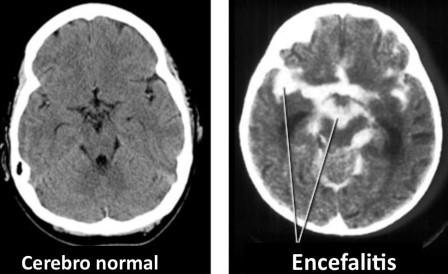

Luego, el personal médico realizó una secuenciación de genes en muestras de su líquido cefalorraquídeo y confirmó la presencia del nuevo coronavirus, diagnosticando al paciente COVID-19 con encefalitis, una inflamación del cerebro.